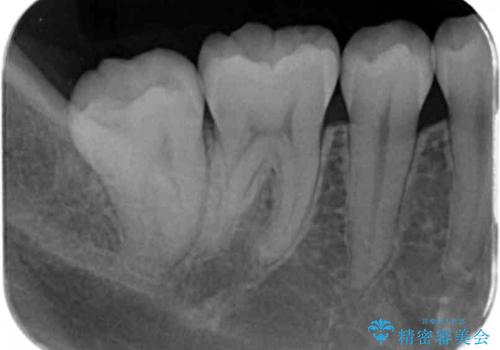

- 奥歯の溝の黒ずみが気になるとのことで来院されました。

変色しない材料をご希望されたためセラミックインレーでの治療となりました。

- 右下7 セラミックインレー 77,000円費用は治療当時の料金となります

樹脂は変色していきますがセラミックは変色しない材料であるため、長く使いたい方にお勧めです。